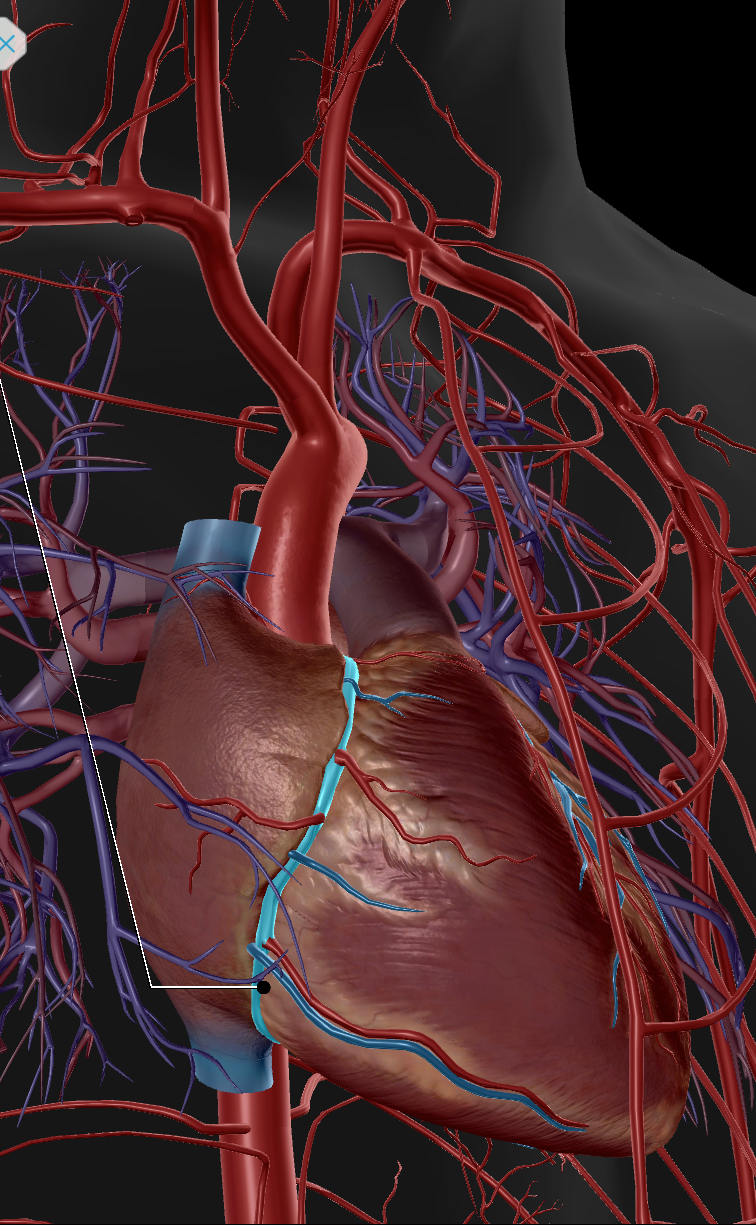

Inferior Vena Cava

Superior Vena Cava

Pulmonary Trunk

Anterior Interventricular Artery

Circumflex Branch

Coronary Artery

Middle Cardiac Vein

Coronary Sinus

Anterior Interventricular Sulcus

Coronary Sulcus

Small Cardiac Vein

Anterior Cardiac Vein

Posterior Interventricular Sulcus/Artery

Coronary Veins

Marginal Branch

Circumflex Artery

Great Cardiac Vein

Pulmonary Artery

Pulmonary Vein